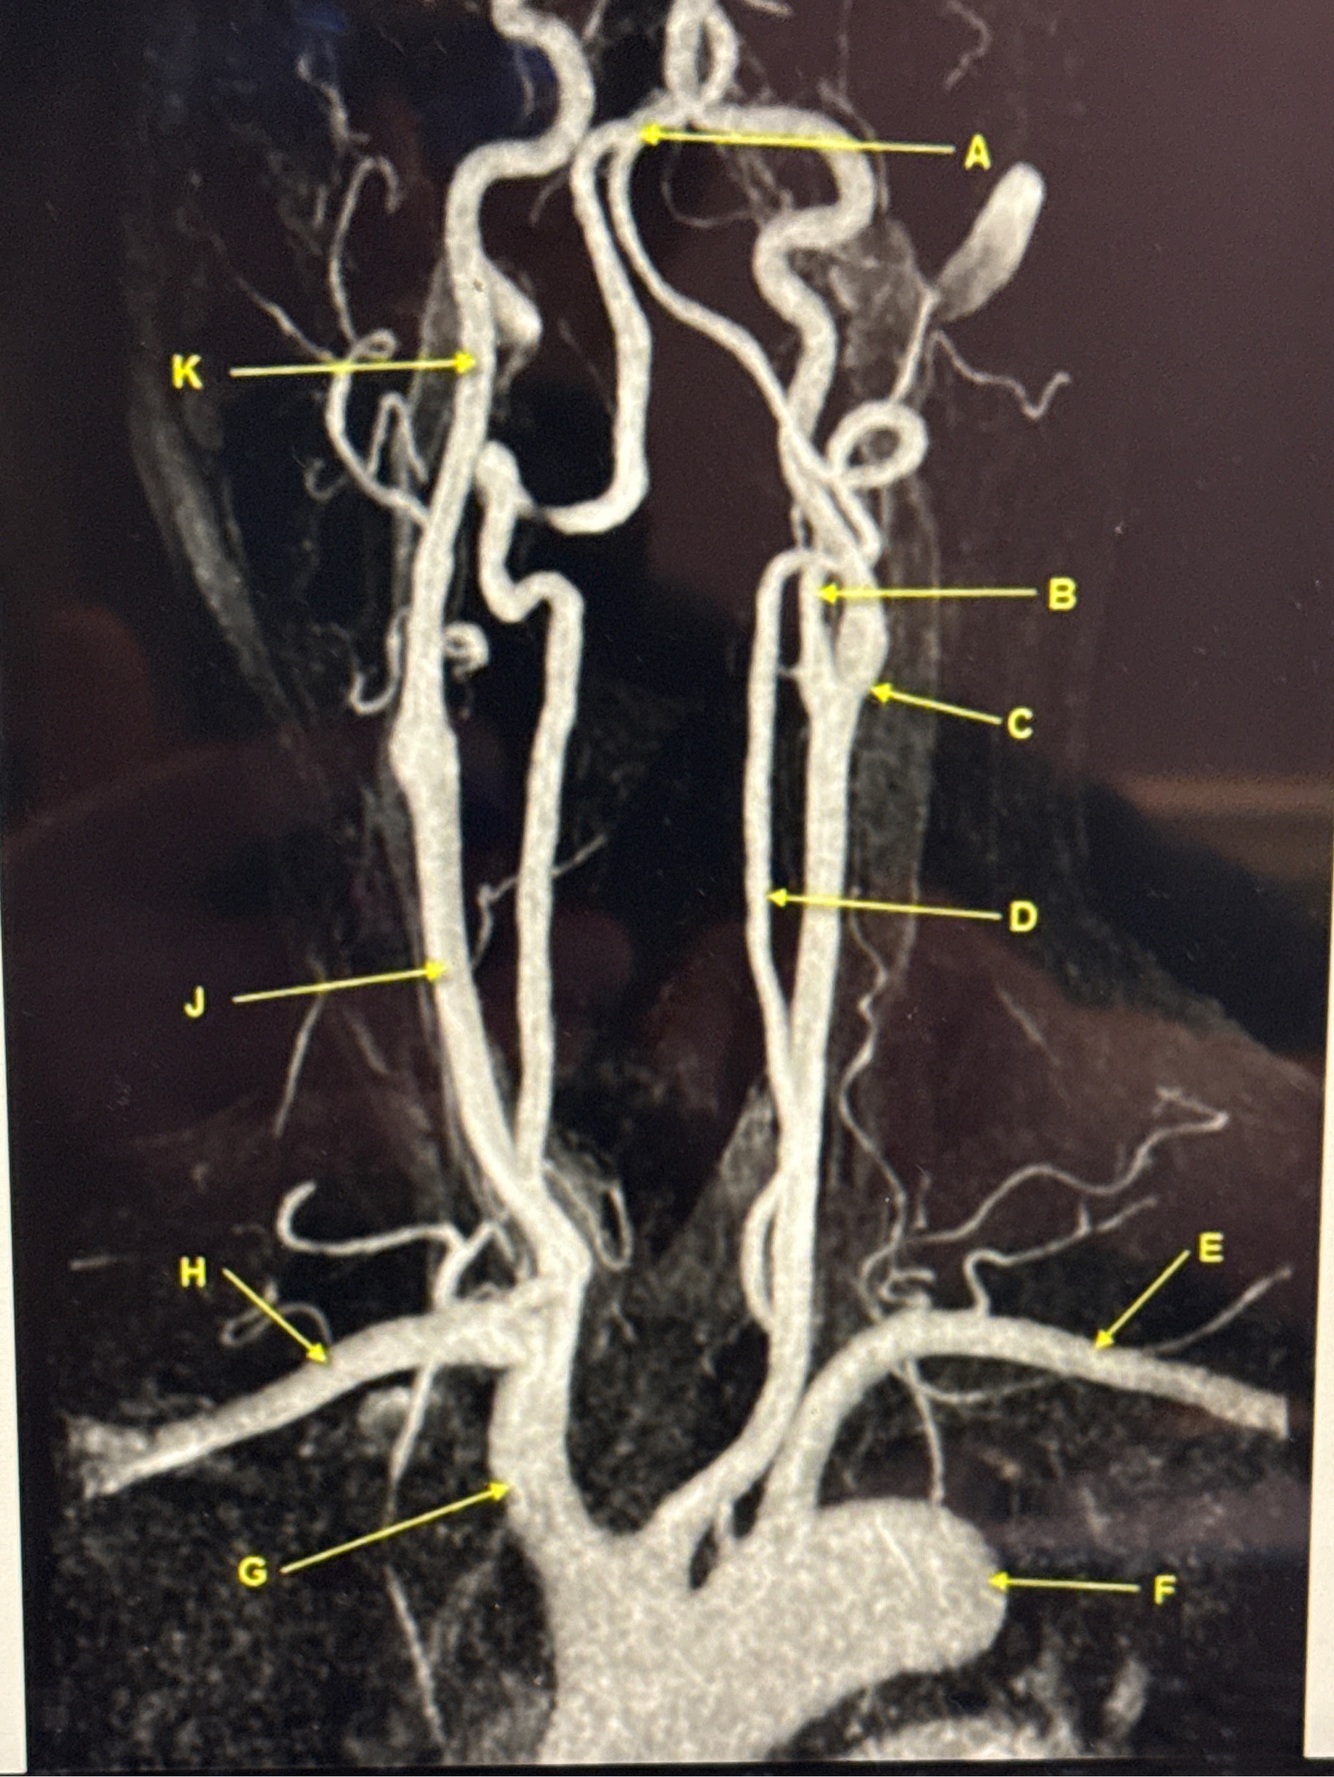

What kind of MR image

MRA EXTRACRANIAL CIRCULATION

Letter B points to

Letter J points to

Letter A points to the

Letter E points to the

Letter K points to the

Letter C points to the

VertebroBasilar junction

Letter B points to the _______ and letter D points to the ______

B. External carotid artery

D. Vertebral artery

Letter E points to the _____ and letter F points to the _____

E. Left subclavian artery

F. Thoracic aorta

Letter G points to the _____ , letter H points to ______ and letter J points to the

G. Brachiocephalic

H. Right subclavian artery

J. Common carotid artery

Letter K points to the ________,

K. Internal carotid artery